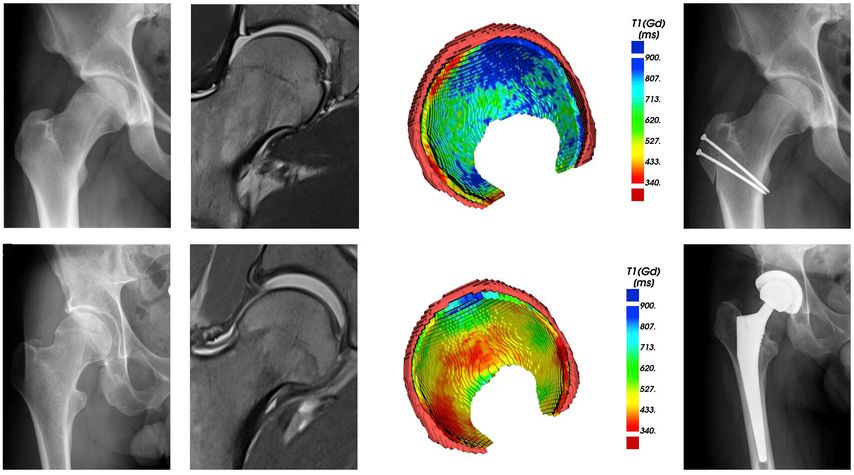

Fig. 2: 3D models of hip cartilage and labrum with color-coded dGEMRIC indices to visualize biochemical cartilage degeneration (red color, black arrowheads) which was confirmed during surgery (white arrowheads).

More recently, we introduced a deep-learning-based approach for automatic segmentation of hip cartilage and labrum using a 3D dGEMRIC sequence (MP2RAGE). The approach allows for automatic and reliable generation of 3D models of hip cartilage and labrum within seconds, and providing both 3D morphologic information of the hip joint as well as color-coded dGEMRIC indices for quantitative analysis of cartilage damage (Fig. 2 & 3).19

Fig. 3: Two patients with cam deformity of the proximal femur. Pelvic X-ray shows in both cases only mild arthritic changes. The morphologic MRI only allows 2D morphologic assessment of damage. The 3D cartilage models allow for a quantitative and 3D assessment of cartilage degeneration. Compared to the patient with good cartilage quality (blue color coding) who underwent impingement surgery the patient below showed too advanced signs of cartilage damage (red color coding) and thus underwent total hip replacement.